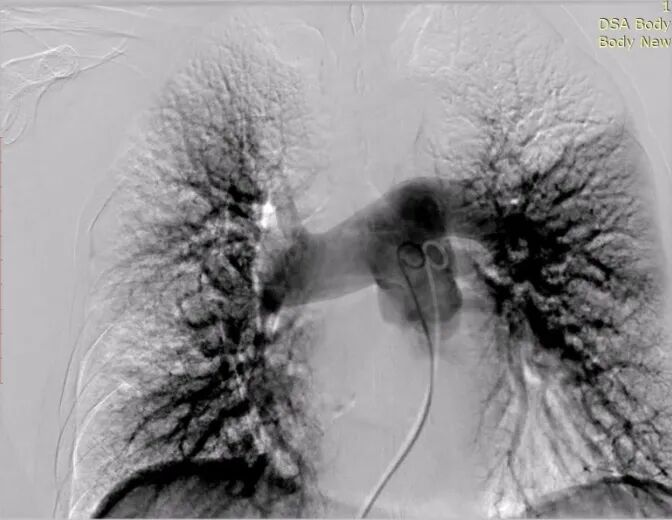

术中

患者双肺血栓负荷大,且氧饱和度较低,为降低肺栓塞的高危恶化风险,仔细评估手术风险和指征,拟行经导管肺动脉取栓术。术中建立右心房-右心室-肺动脉通路,抽吸导管沿导丝送至肺动脉,管口贴近血栓处停止,撤出内芯,将取支架沿导丝通过抽吸导管向前推送,再回撤输送鞘,支架自动打开,连接负压抽吸器,回撤取栓支架的同时旋转开关释放负压,血栓在支架及负压的作用下进入抽吸导管中并带出体外。